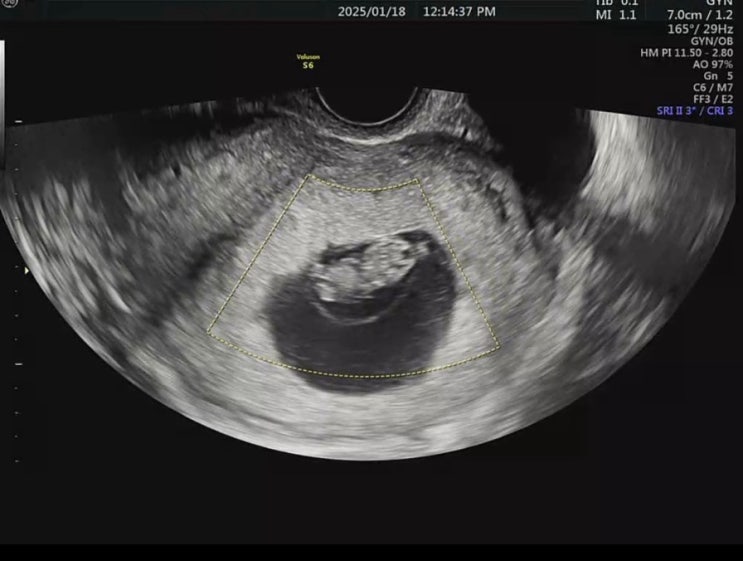

임신 8주차 초음파 젤리곰 천사링 8주차심장박동수

임신8주차 초음파 6주에 심장 박동수 120bpm듣고 어벙벙했던,,, 2주동안 꾹 참고 출산하게될 병원으로 예약...

자궁외임신 후 임신 갑자기 찾아온 아기천사 5주차 6주차

9월말에 알게된 나의 첫 임신은 자궁외임신으로 복강경수술로 종결 되었다 이박삼일 입원.. 유사산휴가 삼...